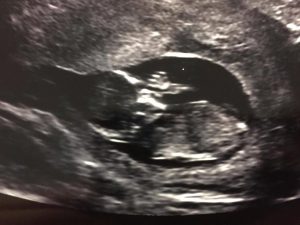

One of my intended dads got to be here on Friday, and even though it was just for a day, it was the 12 week ultrasound. The baby is growing perfectly and was dancing around inside my uterus. (Which was super strange because I could see it on the screen, but couldn’t feel anything. LOL) And of course, just like ALL my other pregnancies, this baby did not want to be in the proper position for the NT measurement, so I get to go again in a few days and hope for the best. (I never ended up getting the measurements for my previous 2 pregnancies because of the position the baby needs to be in, so I’m not holding my breath.)

There it is! In all its glory, with all ten fingers and ten toes.

They were pretty surprised you could see the whole hand.

It was the sweetest moment for me <3